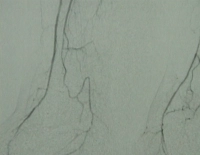

DSA preoperatoria del paciente:

Abb. 1: Hochgradige Arteriosklerose der terminalen Aorta und der Beckenstrombahn bds.

PM 311-2

Abb. 2: Langstreckiger Verschluss der A. femoralis superficialis bds.